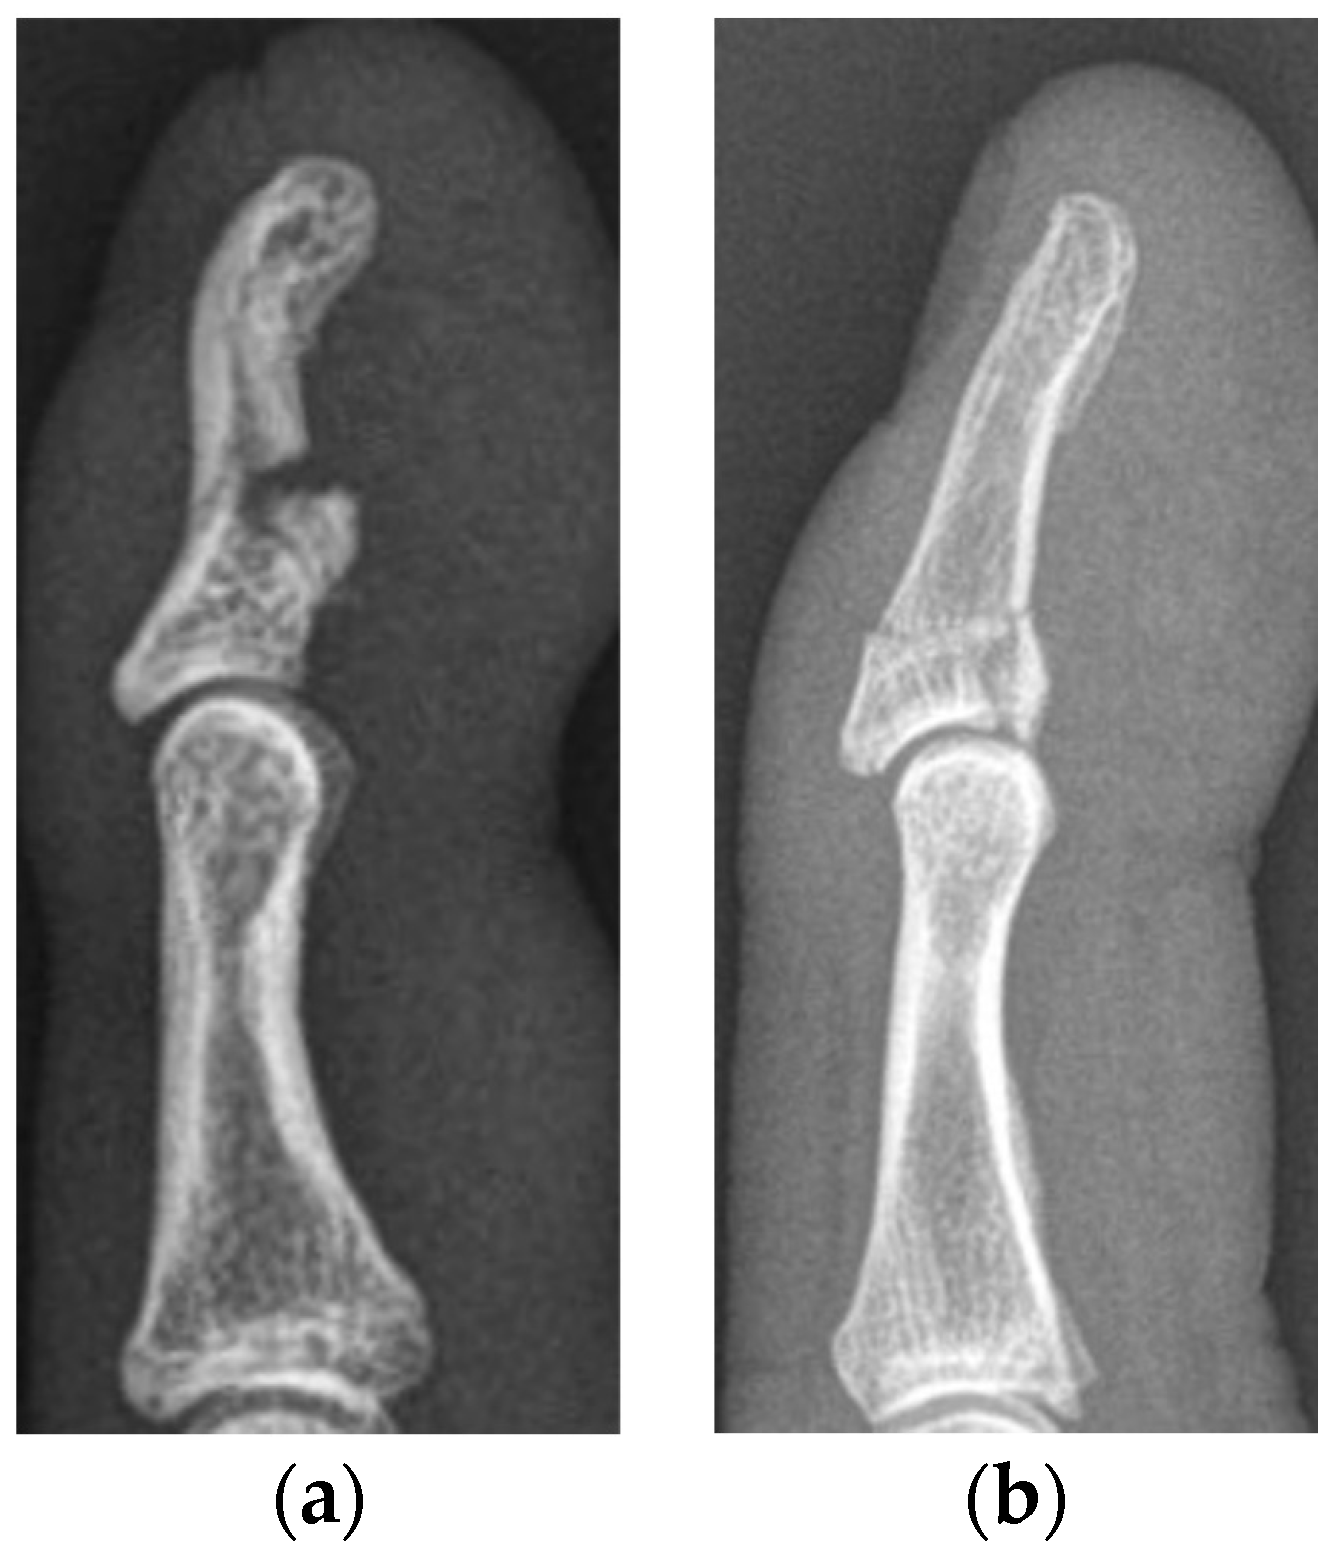

The median primary bony displacement in patients with SD injuries was 5.8 mm (1.2–6.3 mm) and the median articular step-off 2.5 mm (0.9–3.9 mm). The functional outcome in cases who subsequently underwent surgery was poor in two and good in one patient. The patients with a poor outcome developed osteoarthritis grade 4 according to the Kellgren–Lawrence Score within 6 months, resulting in complete stiffness of the DIP joint. Their injuries were reconstructed with the help of a Bunnell pull-out suture and a K-wire in one patient and with three K-wires in the other. The patient receiving reconstruction with the Bunnell pull-out suture lost the ulnar part of his nail due to the refixation. The patient with a good outcome received reconstruction with a mini-cortical screw and a K-wire (Figure 4).

Figure 4. Lateral radiographs of a type Vb jersey finger, with severe displacement of the bony fragments and a resulting articular step-off (a). The same patient after surgical refixation using a mini-cortical screw and a K-wire (b). Lateral radiographs after K-wire removal 6 weeks after surgery (c). The functional outcome of this patient was classified as good.